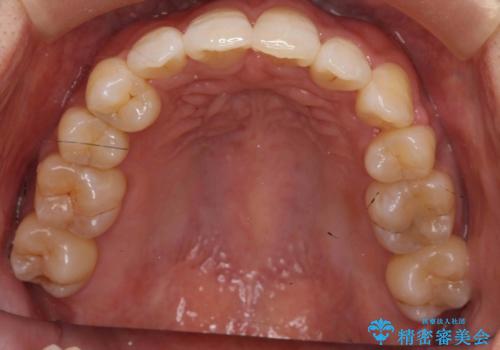

右上以外の3本を抜歯しきちんと並べました。

前歯も引っ込み、口が閉じやすくなりました。